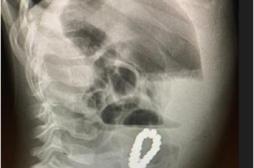

LES MALADIES